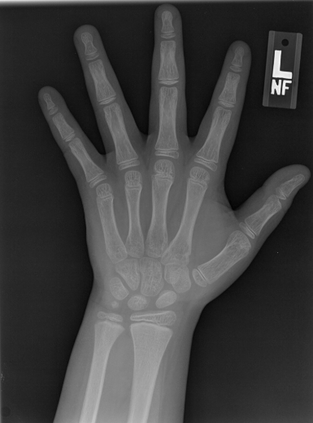

Deep neural networks are increasingly being used for the analysis of medical images. However, most works neglect the uncertainty in the model's prediction. We propose an uncertainty-aware deep kernel learning model which permits the estimation of the uncertainty in the prediction by a pipeline of a Convolutional Neural Network and a sparse Gaussian Process. Furthermore, we adapt different pre-training methods to investigate their impacts on the proposed model. We apply our approach to Bone Age Prediction and Lesion Localization. In most cases, the proposed model shows better performance compared to common architectures. More importantly, our model expresses systematically higher confidence in more accurate predictions and less confidence in less accurate ones. Our model can also be used to detect challenging and controversial test samples. Compared to related methods such as Monte-Carlo Dropout, our approach derives the uncertainty information in a purely analytical fashion and is thus computationally more efficient.